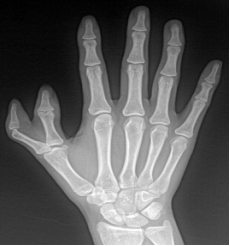

多指畸形

手足短骨解剖及常见疾病的影像学表现